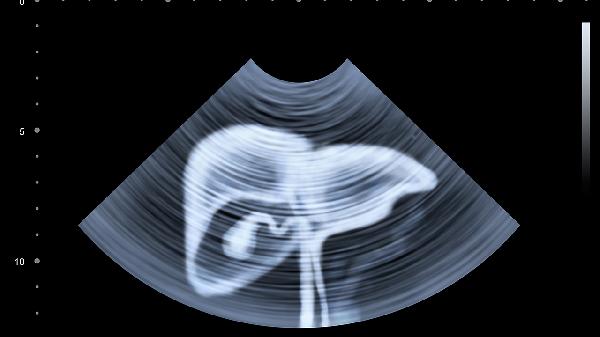

定期监测肝功能是评估恢复情况的重要手段,化疗期间及结束后应每月检查一次。主要观察指标包括谷丙转氨酶、谷草转氨酶、总胆红素等。如指标持续异常,可能需要调整化疗方案或加强护肝治疗。同时需要关注皮肤黄染、食欲下降、乏力等肝损伤症状,出现这些表现应及时就医。对于既往有肝病基础的患者,监测频率可能需要适当增加。